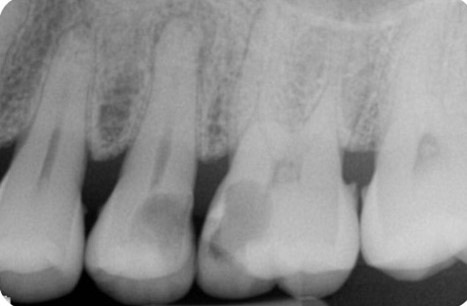

Endodontics is the study and treatment of disorders of the neurovascular tissue within the interior of teeth, including the pulp chamber and roots. These disorders occur most often when the root canal becomes infected as a result of extension of dental caries into the pulp chamber. With infection of the neurovascular tissue, necrosis can occur, and the disease process can progress to involve the entire root canal system (Figure 1). Pain, often intense, will be experienced by the affected individual. As necrotic debris becomes located at the apex of the root in the alveolar bone, the infection can extend beyond the local area to include the more coronal periodontal tissues (Figure 2). Obvious clinical swelling and suppuration can be present. The bacteria that characterize these acute lesions are Gram-negative anaerobes. These infections can be associated with systemic symptoms, including fever and malaise.

Figure 1. Radiograph demonstrating extensive caries of the distal half of the maxillary second bicuspid and mesial half of the maxillary first molar. Apical periodontitis is clearly visible for the second bicuspid and widening of the apical area of the roots of the first molar is suggested. Radiograph courtesy of Drs. Y. Berlin-Brenner and L. Levin.

- Figure 1